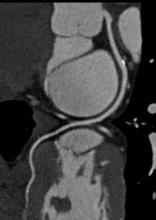

Medtronic Inc. announced clinical trial results showing that heart failure patients treated with its AdaptivCRT feature experienced a nearly 50 percent reduction in atrial fibrillation (AF) risk. Pioneered by Medtronic, the AdaptivCRT technology is a feature on certain cardiac resynchronization therapy-defibrillators (CRT-Ds) that continually adjusts therapy to a patient's natural heart rhythms and minimizes the amount of unnecessary right ventricular (RV) pacing. The results were presented as a late breaking clinical trial at the Heart Failure Society of America's 17th Annual Scientific Meeting.